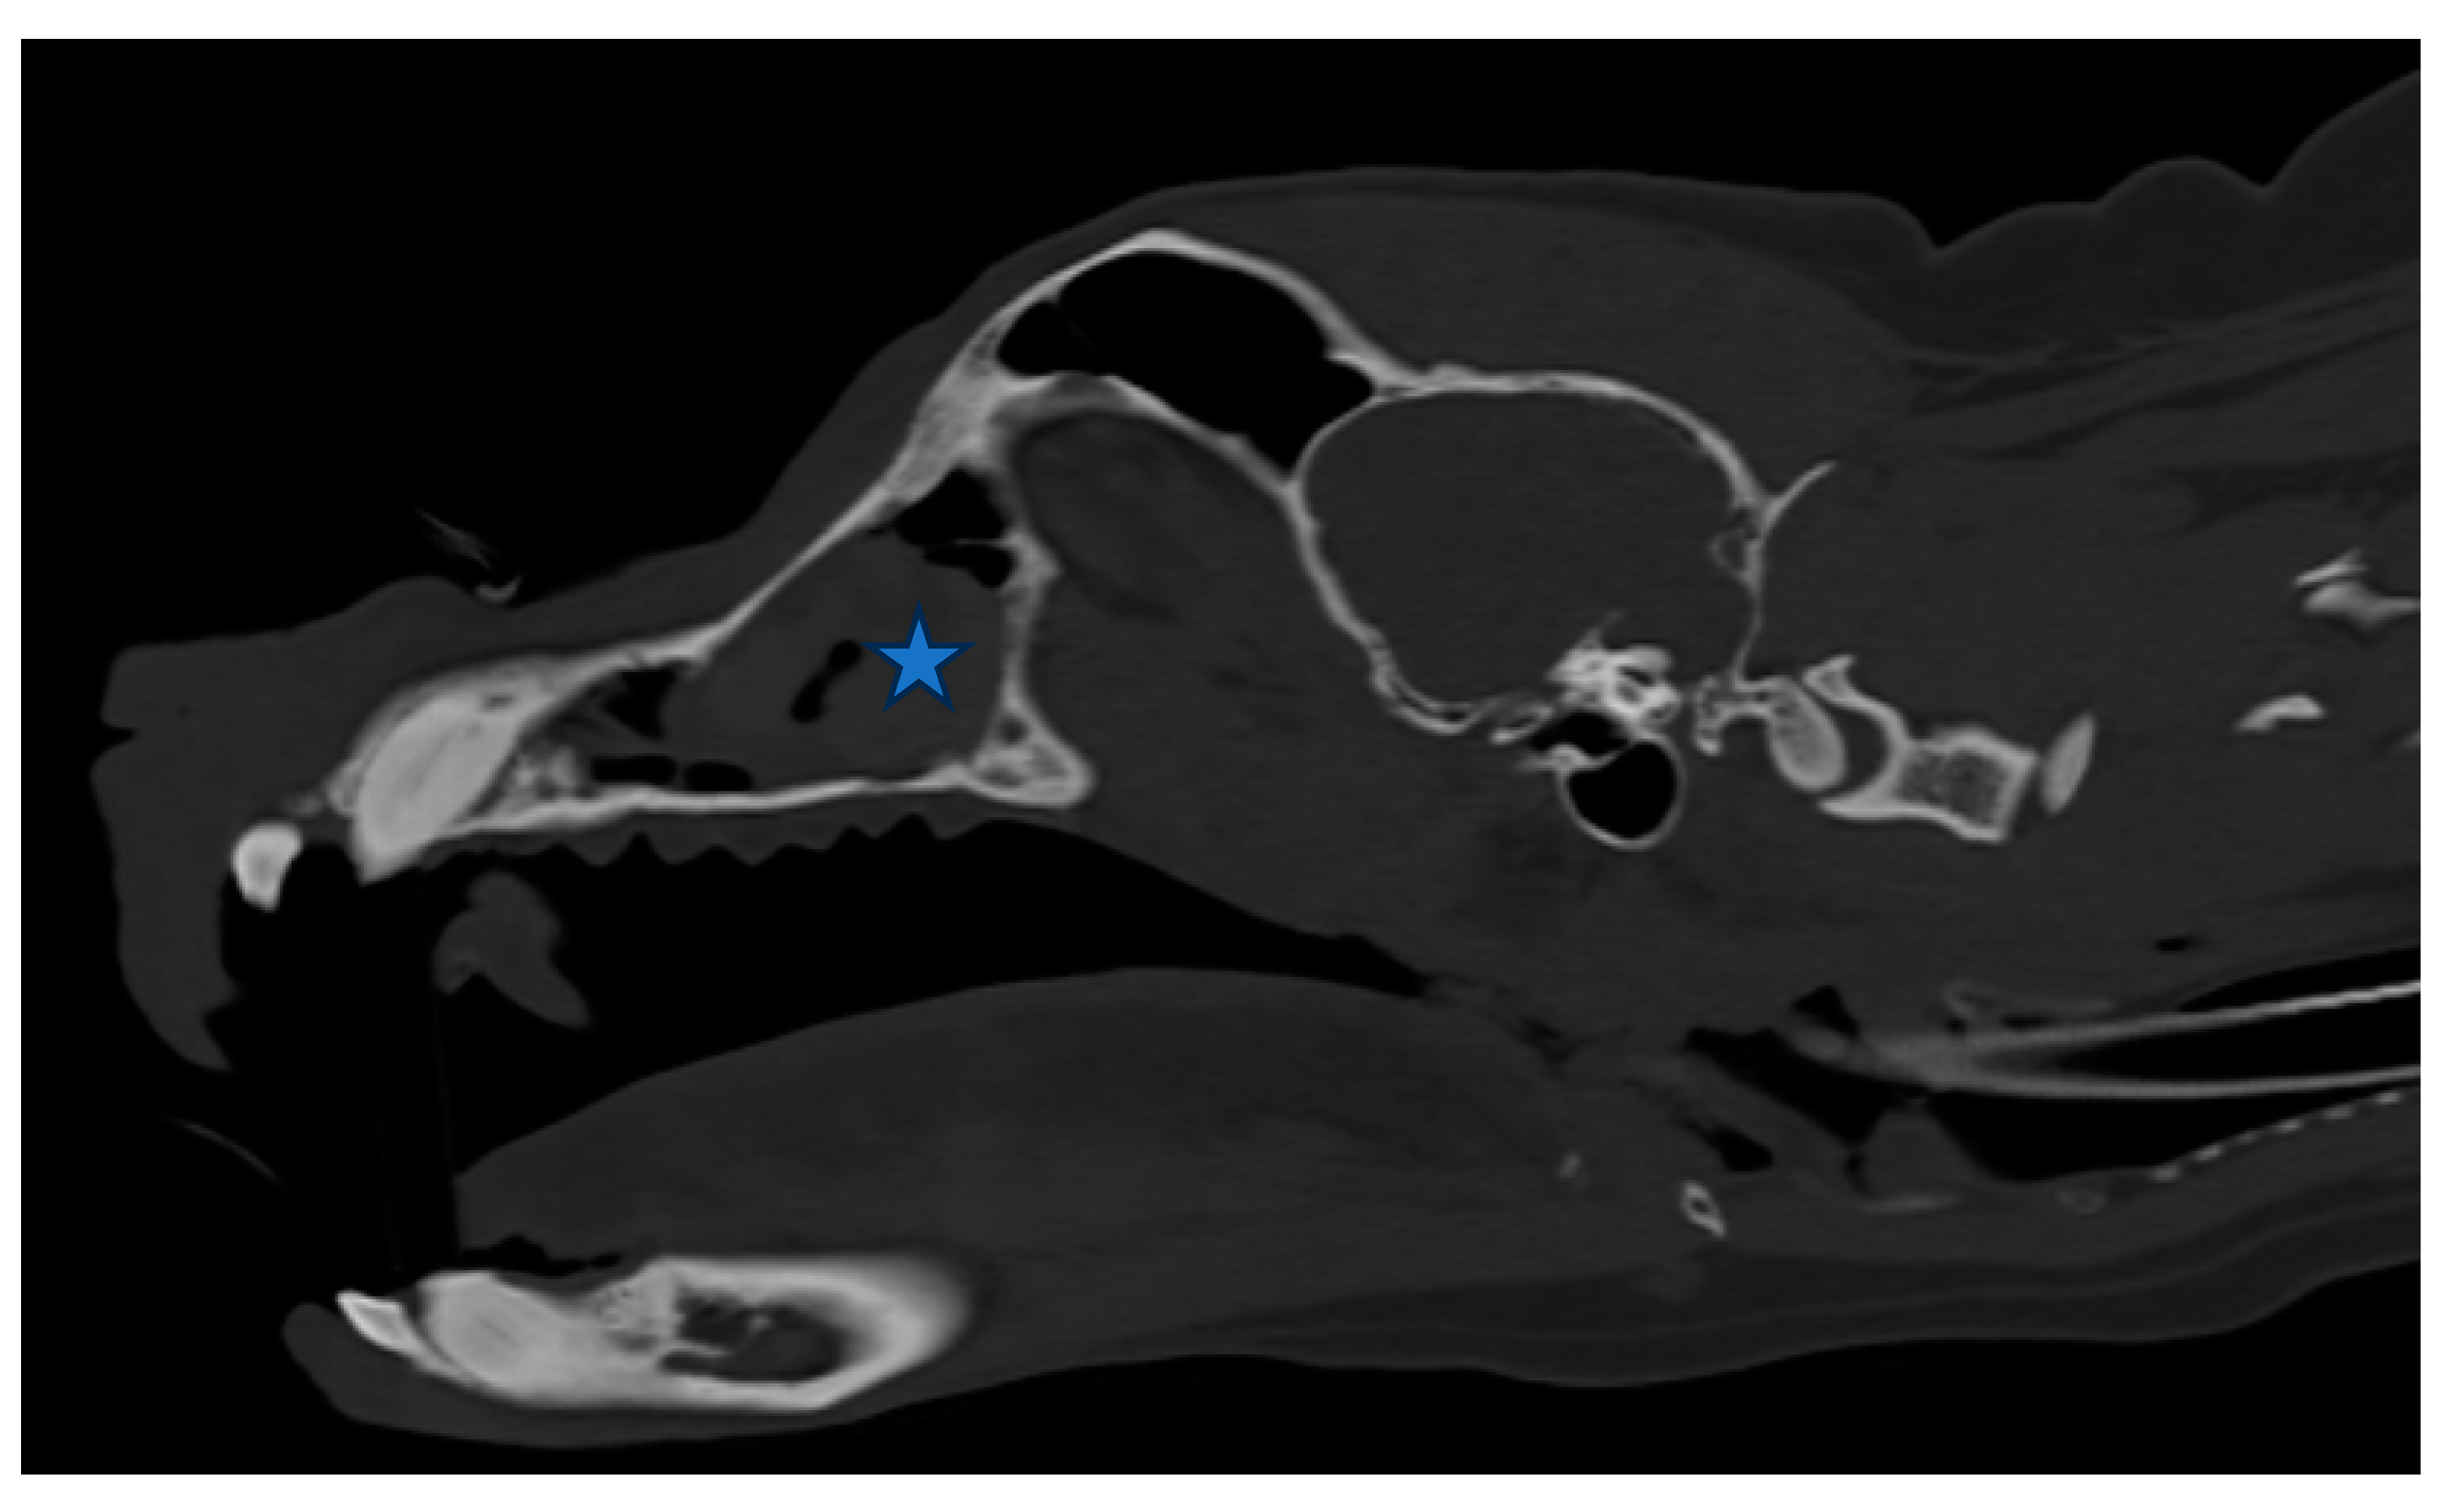

Figure 3. (A,B). Sagittal view of CT scan of skull. The size of the nasal tumor decreased significantly (Asteroid).